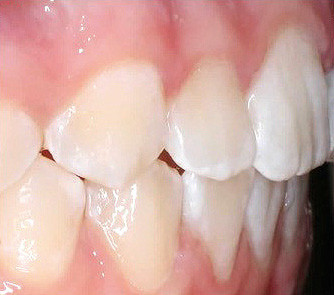

Klinisches Fallbeispiel 2 (Abb. 2a–y)

Distalbiss und tiefer Biss bei einem zwölfjährigen Mädchen. Die Behandlung erfolgte mit Invisalign und Precision Wings. Insgesamt waren zwei Schienensätze notwendig. Die Gesamtbehandlung dauerte 18 Monate.Bei der Planung des ClinCheck wurde der tiefe Biss vorwiegend über eine Intrusion der Unterkieferfront behoben, um die Lachlinie der Patientin nicht negativ zu beeinflussen. Die Oberkieferfront wurde nur retrudiert, jedoch vertikal nicht intrudiert. Während der Phase des Mandibular Advancement wurde die Wirkung der Precision Wings durch den Einsatz von Klasse II-Gummizügen unterstützt. Schlussendlich wurde auch der hängenden Okklusionsebene durch eine einseitige Intrusion der Molaren im ersten Quadranten Rechnung getragen.